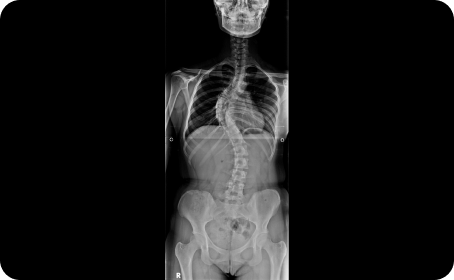

척추의 부정렬이 있는지 확인하는

체형검사, 엑스레이 검사